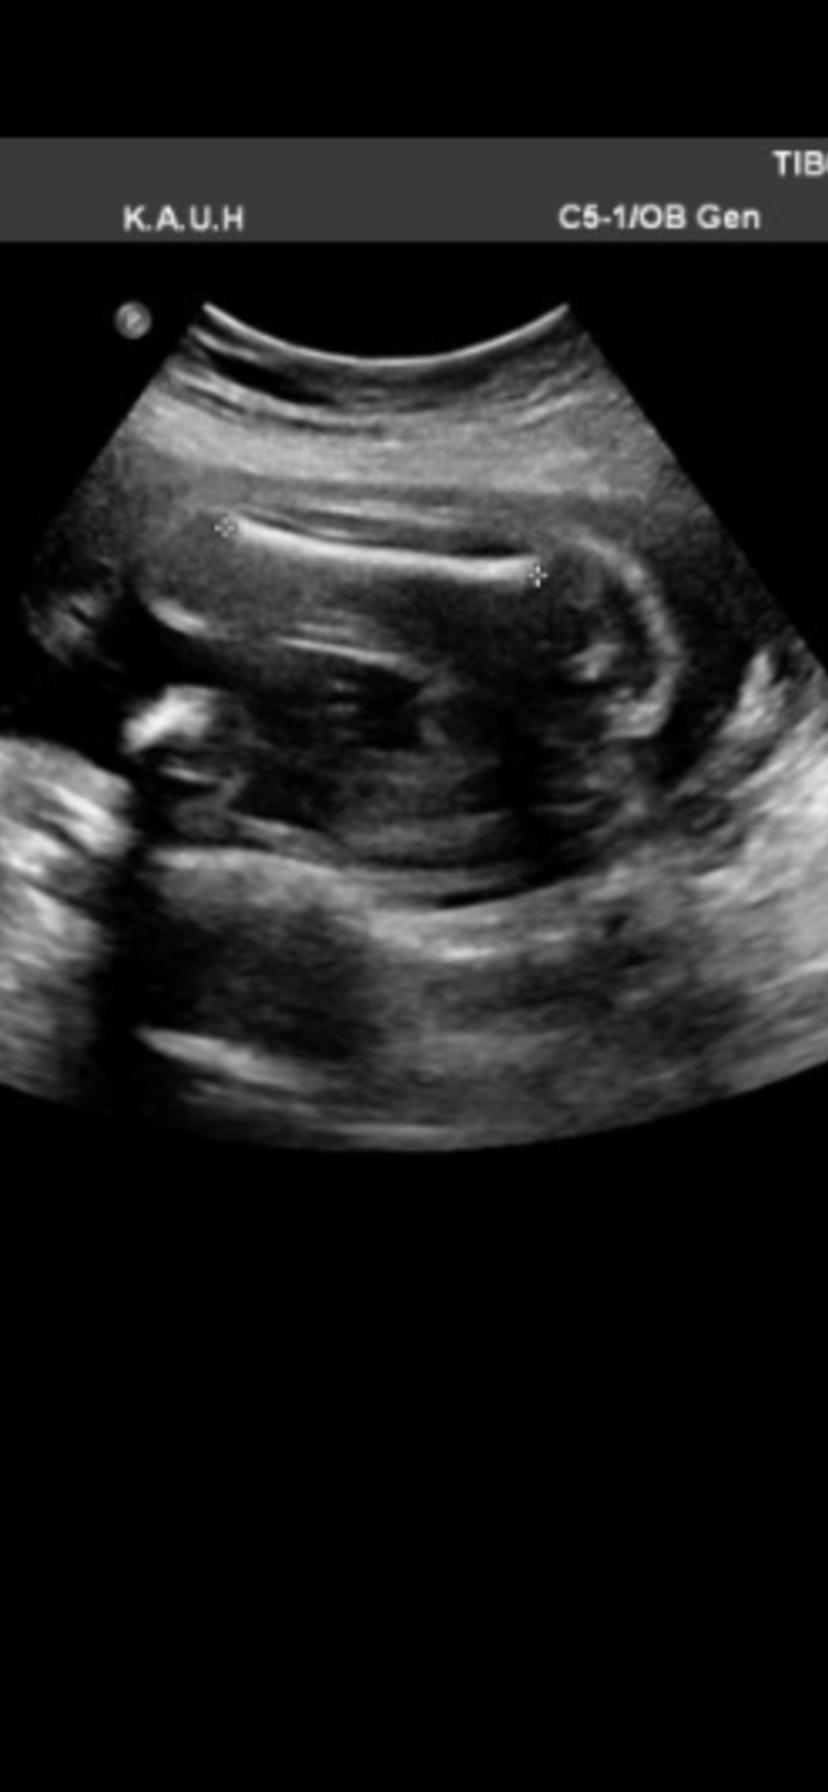

تعالوا لقيت صوره للعضو

يلا استفتاء نتونس الين احجز موعد واتأكد من الجنس

تعالوا لقيت صوره للعضو يلا استفتاء نتونس الين احجز موعد واتأكد من الجنس

ولد واضح البنت يجي كنه برغر